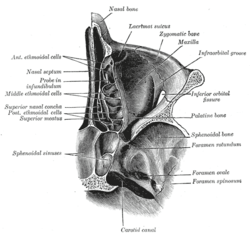

Orbital bones Lateral wall of nasal cavity, showing ethmoid bone in position.

Lateral wall of nasal cavity, showing ethmoid bone in position. Articulation of nasal and lacrimal bones with maxilla.